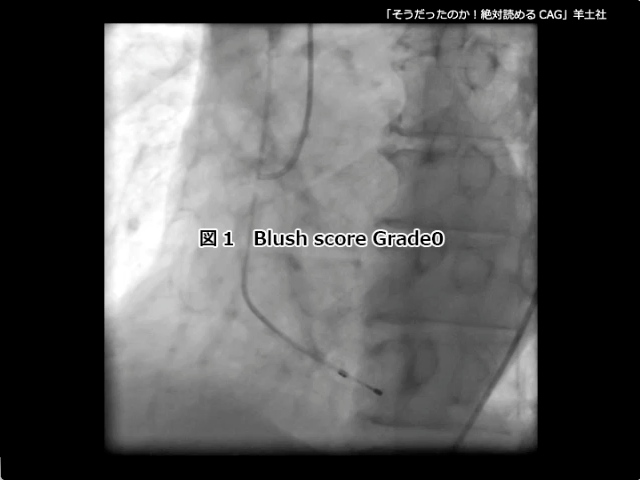

第5章-1 急性冠症候群の造影所見